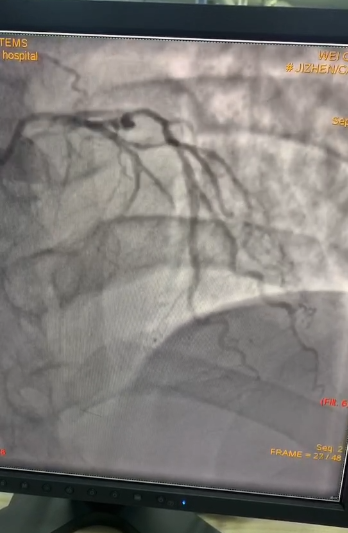

造影提示:前降支闭塞

冠脉球囊快速通过、血流恢复,患者胸痛症状好转。